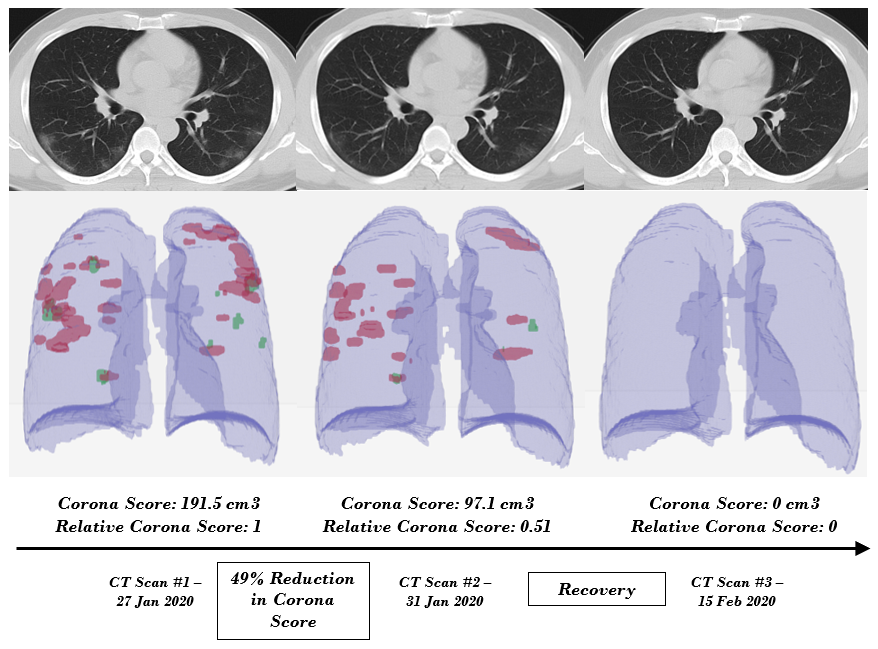

Des Poumons Infectes Par Le Coronavirus Modelises En 3d Youtube

www.youtube.com

Une Video En 3d Permet De Voir A Quoi Ressemblent Des Poumons Infectes Par Le Coronavirus Azertac Video Azerbaijan State News Agency

video.azertag.az

Les Images 3d Des Degats Du Virus Dans Les Poumons Lci

www.lci.fr

3 D Video Shows Covid 19 Attack Patient S Lungs Cnn Video

www.cnn.com

Eleanor Beardsley On Twitter Look At This Coronavirus Infected Lung From 3d Scanner The Yellow And Red Are Severe Lesions Picture From Paris Match Magazine Caption Says In Just A Few Days

twitter.com

Cette Video En 3d Montre Des Poumons Infectes Par Le Coronavirus Le Point

www.lepoint.fr